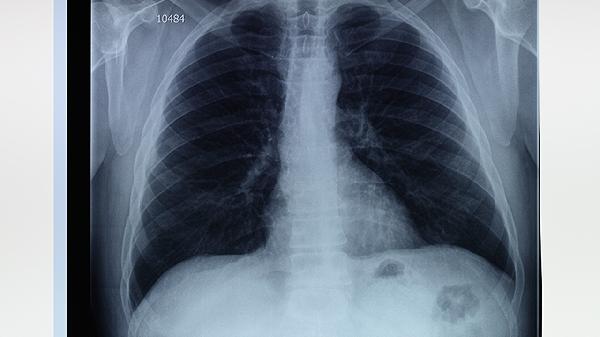

肺大泡患者日常应戒烟,避免接触粉尘和刺激性气体,保持室内空气流通。饮食宜清淡易消化,适量补充优质蛋白和维生素,避免辛辣油腻食物。可进行适度呼吸训练如腹式呼吸,增强肺功能。定期复查胸部影像学,监测肺大泡变化情况。出现呼吸急促、胸痛加重等症状应及时就医,不可自行尝试所谓快速自愈方法。